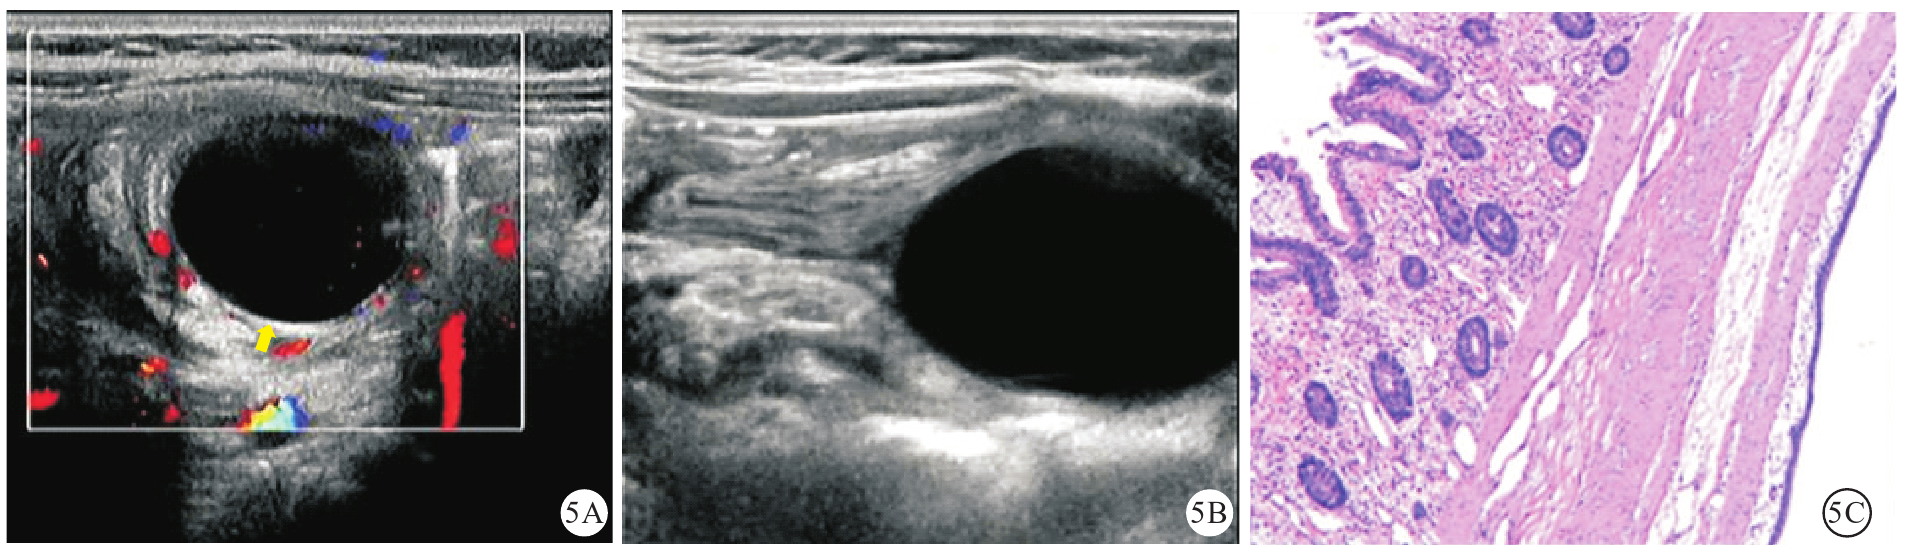

图5 本研究1例肠重复畸形继发性肠套叠患儿(女性,3个月龄)的超声声像图及病理学检查图像[图5A:超声可见肠套叠横断面套筒中央为一囊腔(黄色箭头所示),囊壁为消化道壁结构;图5B:超声可见纵断面囊腔位于套筒头端;图5C:病理学检查结果提示囊腔内衬柱状黏液上皮,局部与肠管壁共肌层(HE染色,低倍)]注:HE为苏木精-伊红